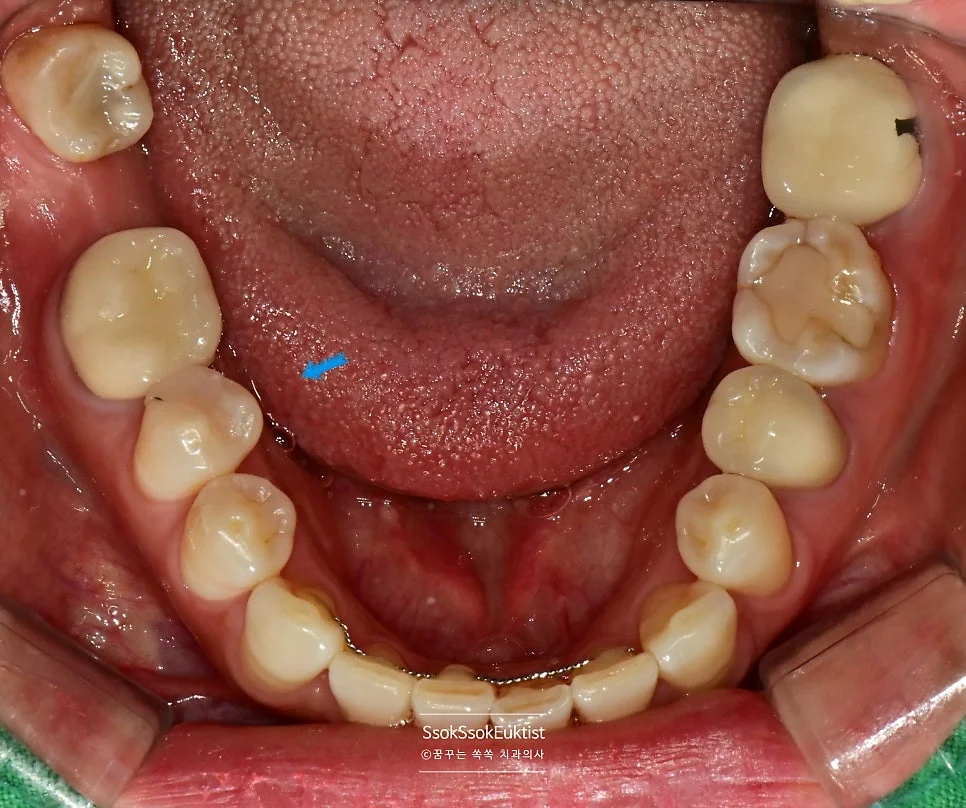

구강 사진에서 하얀색 화살표는 충치의 위치를, 파란색 화살표로는 해당 치아를 번호로 기재하였는데요. 각 치아의 치료 계획에 대해 말씀드리겠습니다.

5번 치아 — 임플란트 인접 충치

5번 치아 — 임플란트 바로 앞 치아의 충치

5번 치아의 경우 임플란트 바로 앞 치아인데요.

임플란트는 움직이지 않는 데 반해 다른 치아는 평생에 걸쳐 가운데로 몰리는 경향이 있어 임플란트의 바로 앞 부분은 시간이 지나면 틈이 생기고 음식물이 잘 끼며, 이것이 방치될 경우 충치로 발전할 수 있습니다.